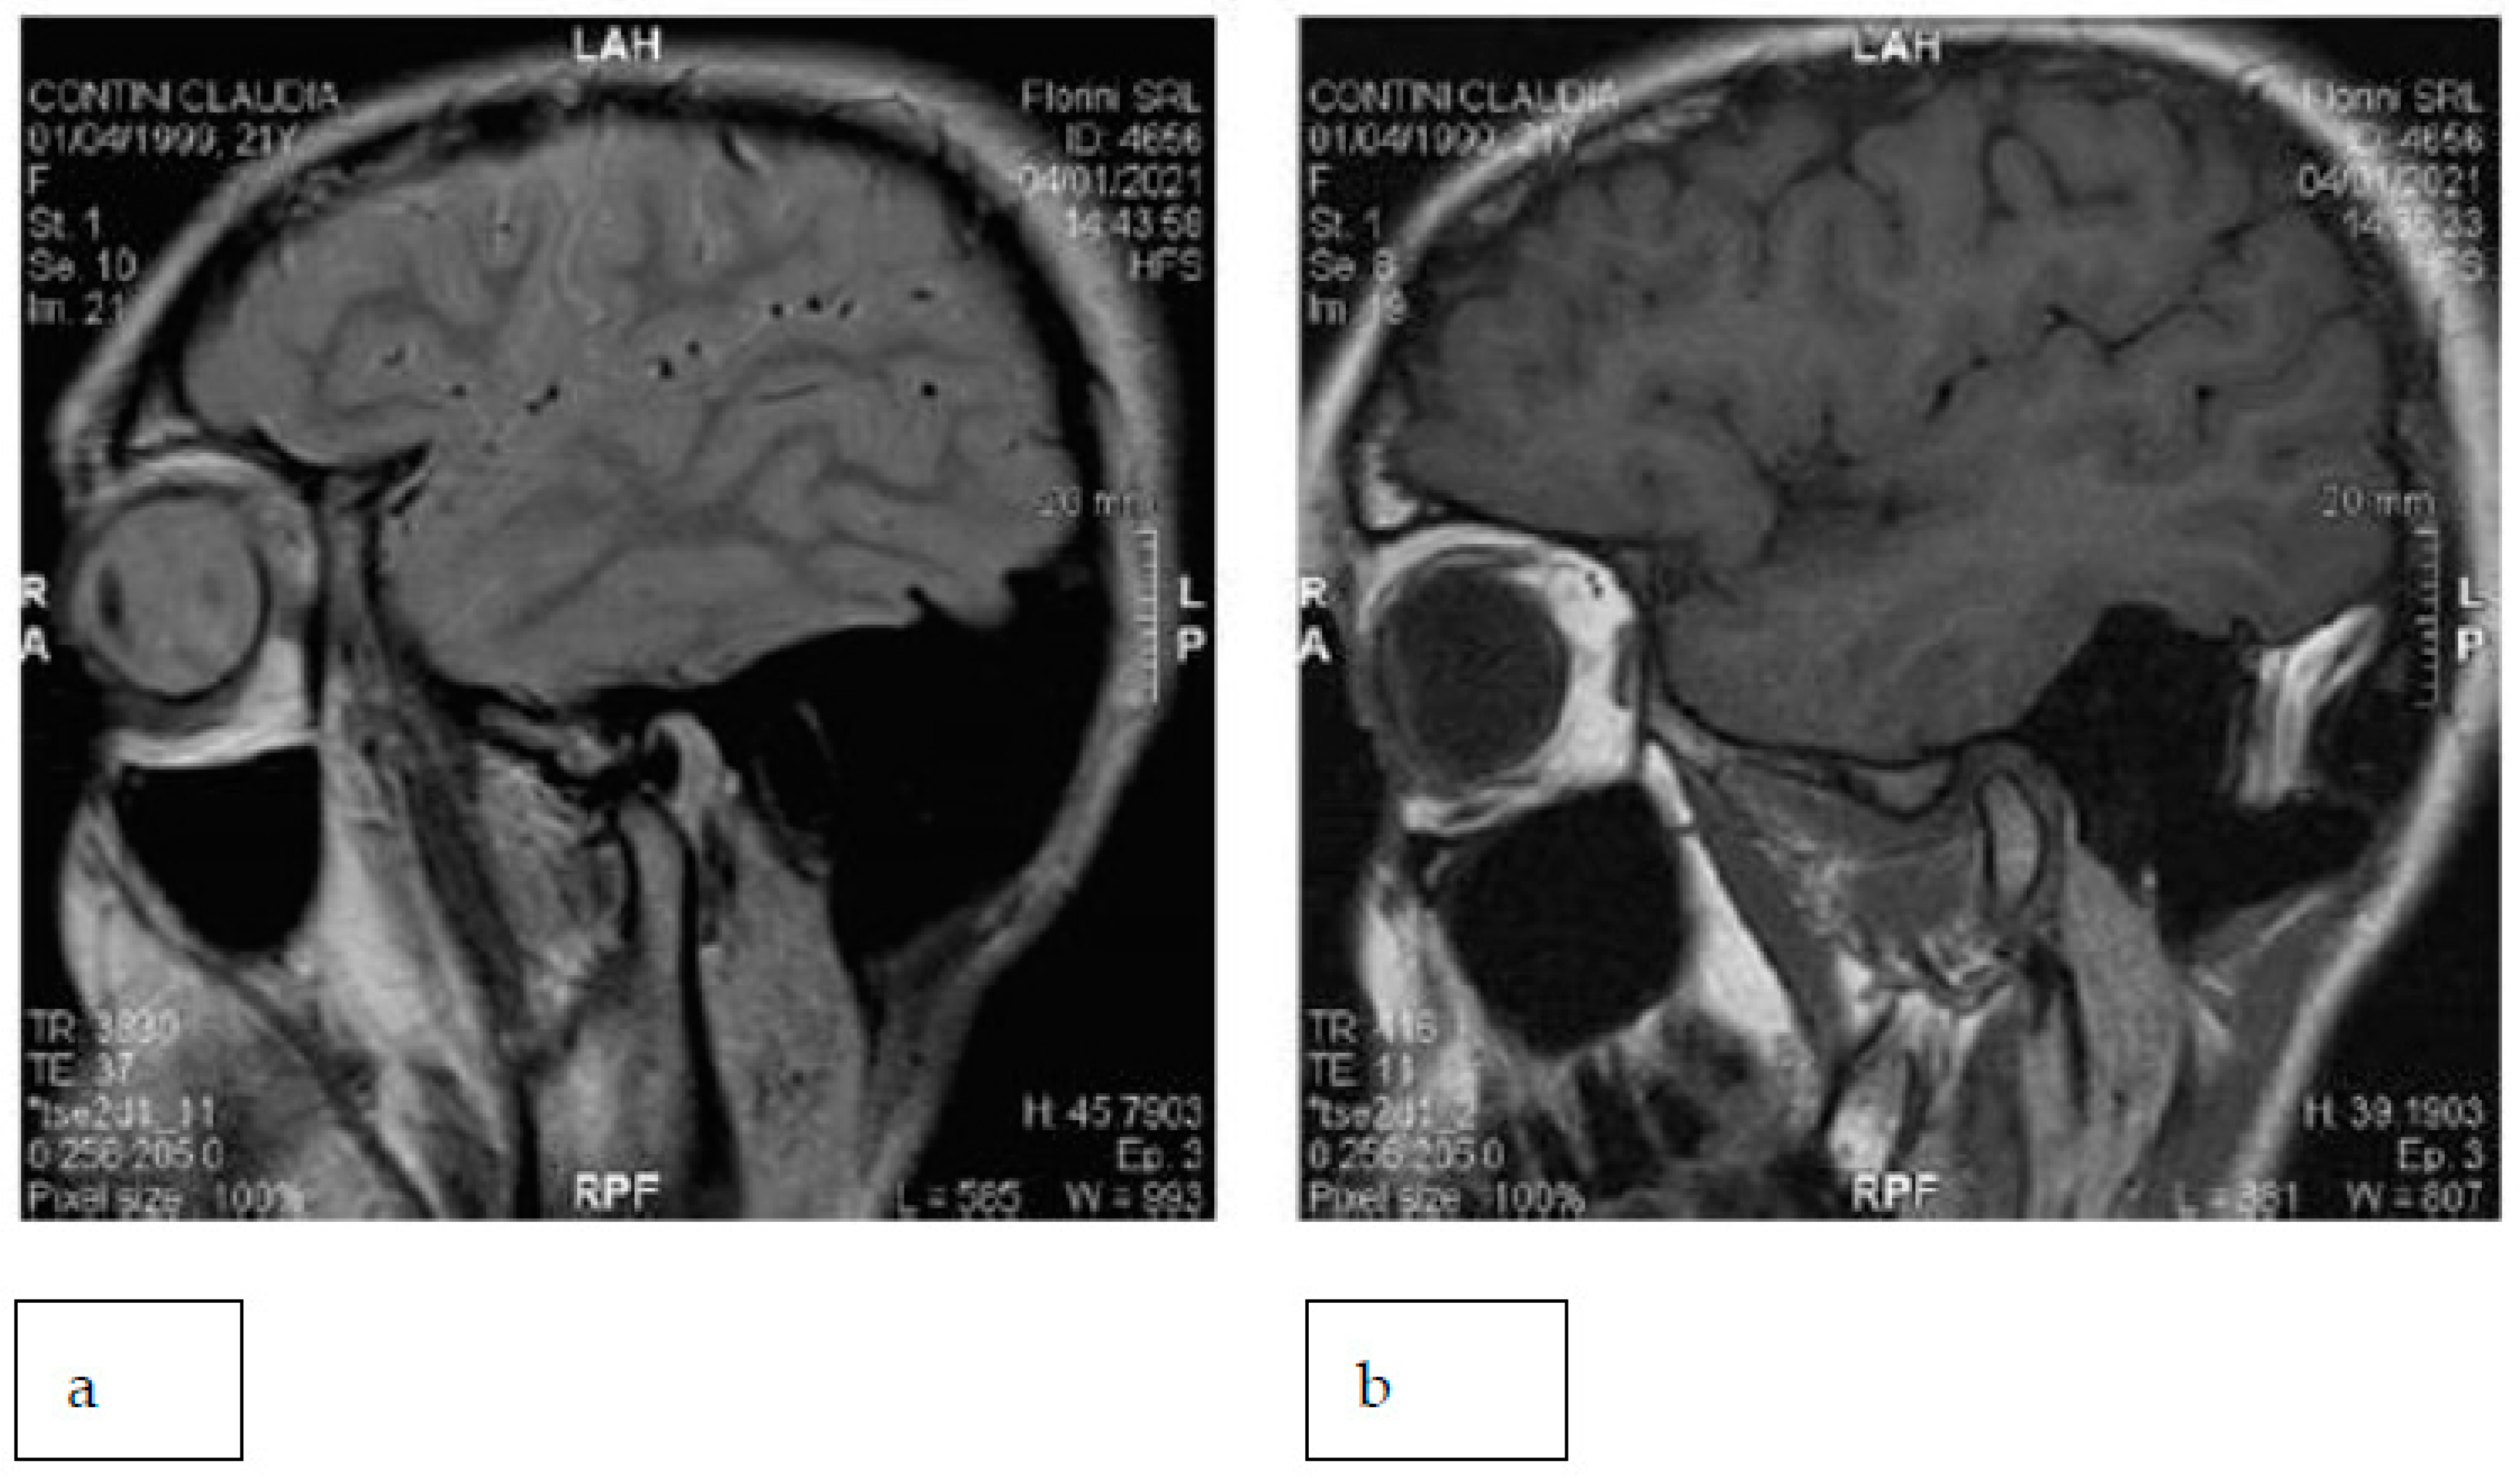

MRI of the TMJs with closed and open mouths showed disc displacement with a reduction in both TMJs (Figure 20).

Figure 20. The right TMJ with an open (a) and closed (b) mouth.